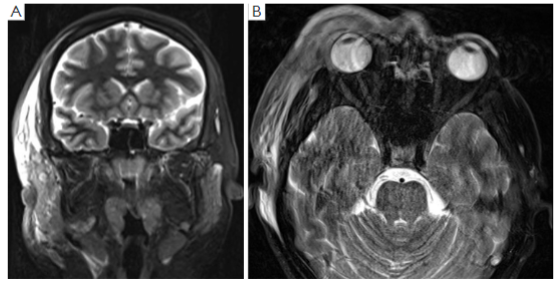

Due to the significant suspicion for NF, the patient was commenced on intravenous (IV) meropenem, clindamycin and vancomycin, and planned for urgent surgical exploration and debridement with the assistance of the Plastics and Reconstructive Surgery unit. Pre-operative T2-weighted magnetic resonance imaging (MRI) demonstrated fascial hyperintensity involving the pre-septal tissues and extending to the anterior temporal fossa (Figure 2A,2B).

Figure 2 Pre-operative T2-weighted magnetic resonance imaging. (A) Coronal and (B) axial, demonstrating the fascial hyperintensity involving the pre-septal tissues and extending to the anterior temporal fossa.